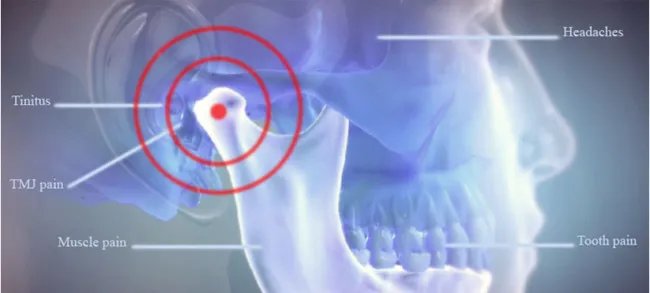

When it becomes strained, inflamed, or misaligned, it triggers discomfort that can radiate to your head, neck, and ears.

Common TMJ Disorder Symptoms You Shouldn’t Ignore

- Jaw clicking or popping when chewing

- Pain or stiffness around the jaw joint

- Difficulty opening or closing your mouth

- Ear pain, headaches, or neck soreness

- Locking of the jaw during movement

If you have two or more of these TMJ disorder symptoms, it’s time to consider expert TMJ treatment Bangalore — before it worsens.